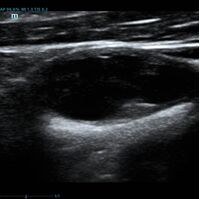

Современное решение – компьютерный анализ структуры бляшки. Ультразвуковая система экспертного класса Mindray DC-8 способна провести программный анализ полученного изображения бляшки и дать количественную оценку её структуры. Для этого используется показатель GSM – Grey Scale Median. Прибор рассчитывает медиану по показателям серой шкалы в выделенной зоне и выдает данные в виде графика распределения эхогенности и числовых данных для количественной оценки. Таким образом, исследование становится более объективным и воспроизводимым, снижается зависимость от оператора (человеческого фактора).